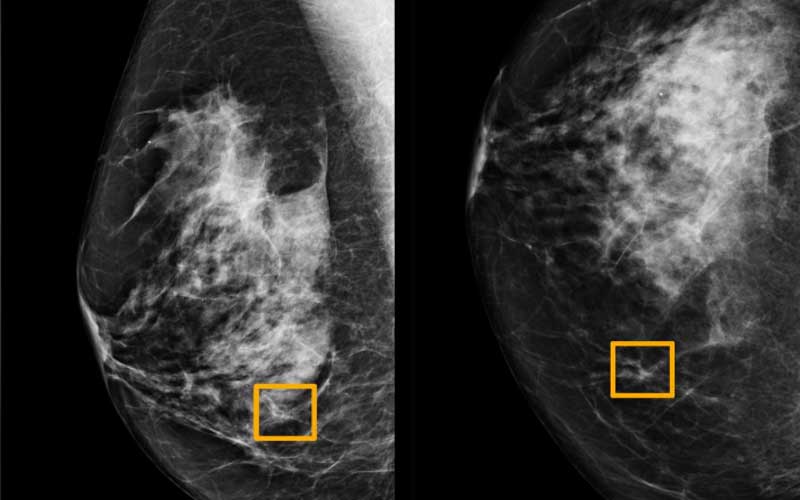

A Google artificial intelligence system proved as good as expert radiologists at detecting which women had breast cancer based on screening mammograms and showed promise at reducing errors, researchers in the United States and Britain reported.

The study, published in the journal Nature on Wednesday, is the latest to show that artificial intelligence (AI) has the potential to improve the accuracy of screening for breast cancer, which affects one in eight women globally. Radiologists miss about 20 per cent of breast cancers in mammograms, the American Cancer Society says, and half of all women who get the screenings over a 10-year period have a false-positive result. The findings of the study, developed with Alphabet Inc’s DeepMind AI unit, which merged with Google Health in September, represent a major advance in the potential for the early detection of breast cancer, Mozziyar Etemadi, one of its co-authors from Northwestern Medicine in Chicago, said.

The team, which included researchers at Imperial College London and Britain’s National Health Service, trained the system to identify breast cancers on tens of thousands of mammograms.